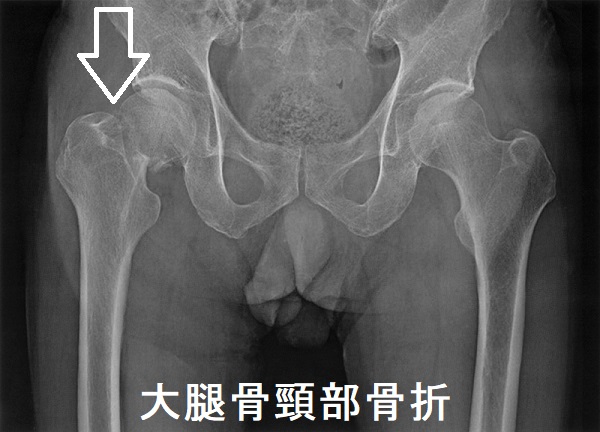

心房細動(Af)や狭心症から甲状腺機能亢進症/バセドウ病がみつかる場合もあります。[Nihon Ronen Igakkai Zasshi. 1996 Mar;33(3):191-5.] - 特に老年期女性は元々、閉経後骨粗鬆症があるため、さらに骨が悪くなる。[高齢者バセドウ病の大腿骨頚部骨折と大腿骨転子部骨折(脚の付け根の骨折)]

加齢による骨粗しょう症で、ただでさへ骨折しやすいのに、高齢の甲状腺機能亢進症/バセドウ病患者は、甲状腺ホルモンの作用で骨分解が加速され、輪をかけて骨折の危険が高くなります(甲状腺機能亢進症/バセドウ病の骨粗しょう症 )。

高齢者の大腿骨頚部骨折後に骨接合術をしなければ寝たきりになり、認知症・筋肉量減少によるサルコペニアが進行します。転倒しやすい生活環境を改善し、ヒッププロテクターを装着するのもよいでしょう。